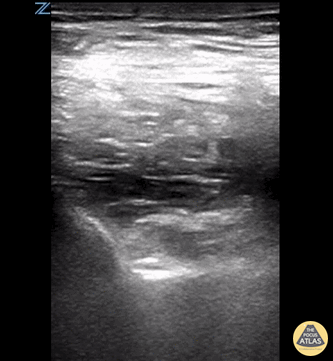

A PENG block was performed using the linear probe. The hyperechoic psoas tendon can be seen lifting off the ileum with the injection of anesthetic. Ariella Cohen MD Eric Quinn MD Maimonides Medical Center Emergency Medicine